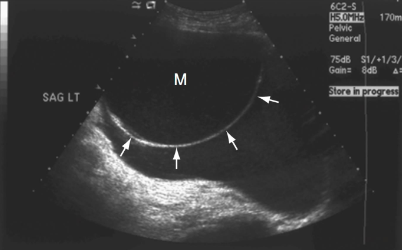

This image displays a

simple cyst